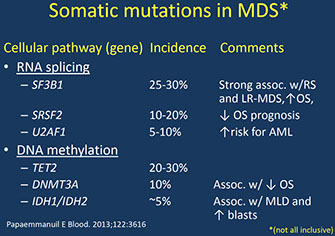

Primary, neoplastic, clonal pluripotent stem cell disorders; karyotype often normal or has abnormalities seen in MDS

- MC in elderly, rare in children, correlates c advancing age, therapy-induced DNA damage and shorter telomeres

MC mutated genes are SF3B1, TET2, SRSF2, ASXL1, DNMT3A, RUNX1, U2AF1, TP53, EZH2

- >50% have chromosome abnormality at dz

- MC cytogenetic abnormalities: deletions of chromosomes 5 and 7, and trisomy 8

- the number and types of translocations are strongly assoc c outcomes; further genetic events assoc c AML

- TP53 mutation eval recommended in pts c iso(5q) bc assoc c resistance to lenalinomide and assoc c worse px

Clonal Hematopoiesis of Indeterminate Potential (CHIP) is acquired clonal mutations identical to those seen in MDS that can occur in hematopoietic cells of apparently healthy older individuals

Intl. Prognostic Scoring System (IPSS) categorizes % blasts, karyotype, and # cell lines c cytopenia and gives px